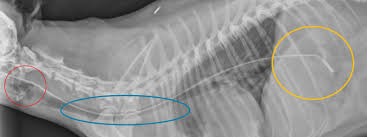

Case Report Catastrophic Heart Failure Vetfolio

Case Report Catastrophic Heart Failure Vetfolio from d36ai2hkxl16us.cloudfront.net